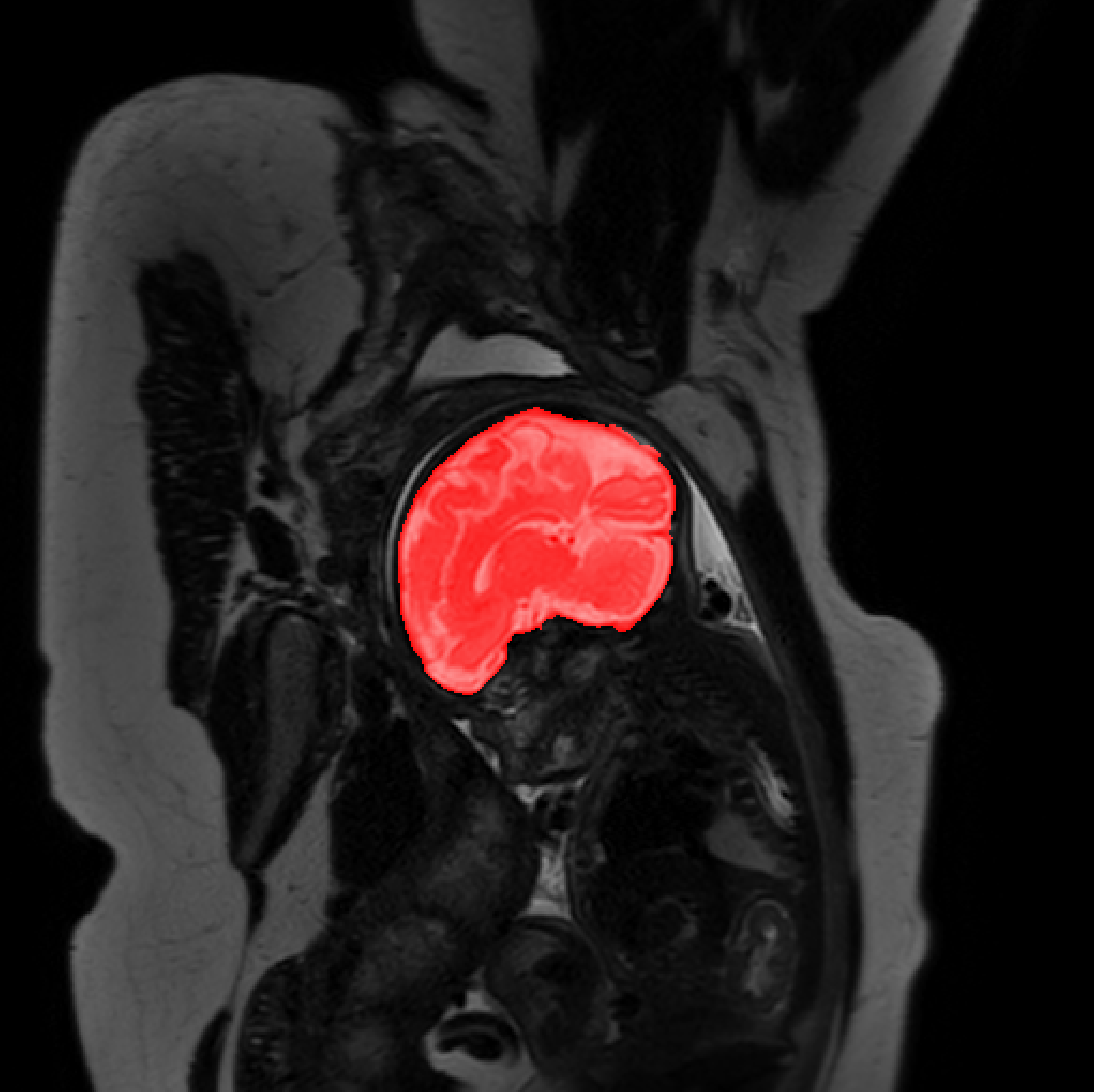

Table 1 lists average of quantitative evaluation results of these experiments and Figure 2 shows results obtained from each image. Figure 3 shows examples of the obtained segmentations.

Refer to caption

Figure 3: Example of ICV segmentations in images acquired in axial (left), coronal (middle) and sagittal (right) planes. Top row: A slice from T2-weigted image; Second row: Automatic segmentations obtained using 7 training images from the representative imaging planes; Third row: Automatic segmentations obtained using all 21 training images from all 3 image orientations; Bottom row: Manual segmentation.